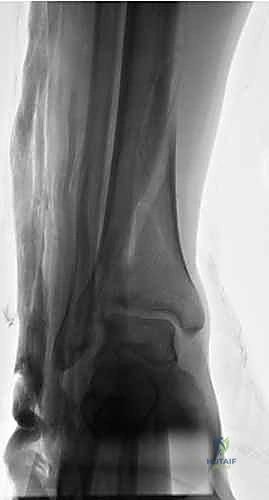

- بروز العظم (في الكسور المفتوحة): خروج شظايا العظم عبر الجلد مع نزيف حاد.

- تورم وكدمات سريعة: نتيجة النزيف الداخلي في الأنسجة المحيطة.

- فقدان الإحساس أو النبض: في القدم، وهو مؤشر خطير جداً (حالة طوارئ قصوى) يدل على تضرر الأعصاب أو الأوعية الدموية.

1. التقييم والتحضير (Pre-operative)

بمجرد وصول المريض إلى الطوارئ، يتم إنعاشه وإعطاؤه المضادات الحيوية الوريدية فوراً (خاصة في الكسور المفتوحة). يتم أخذ صور أشعة سينية وأحياناً أشعة مقطعية (CT Scan) لفهم نمط الكسر بدقة.